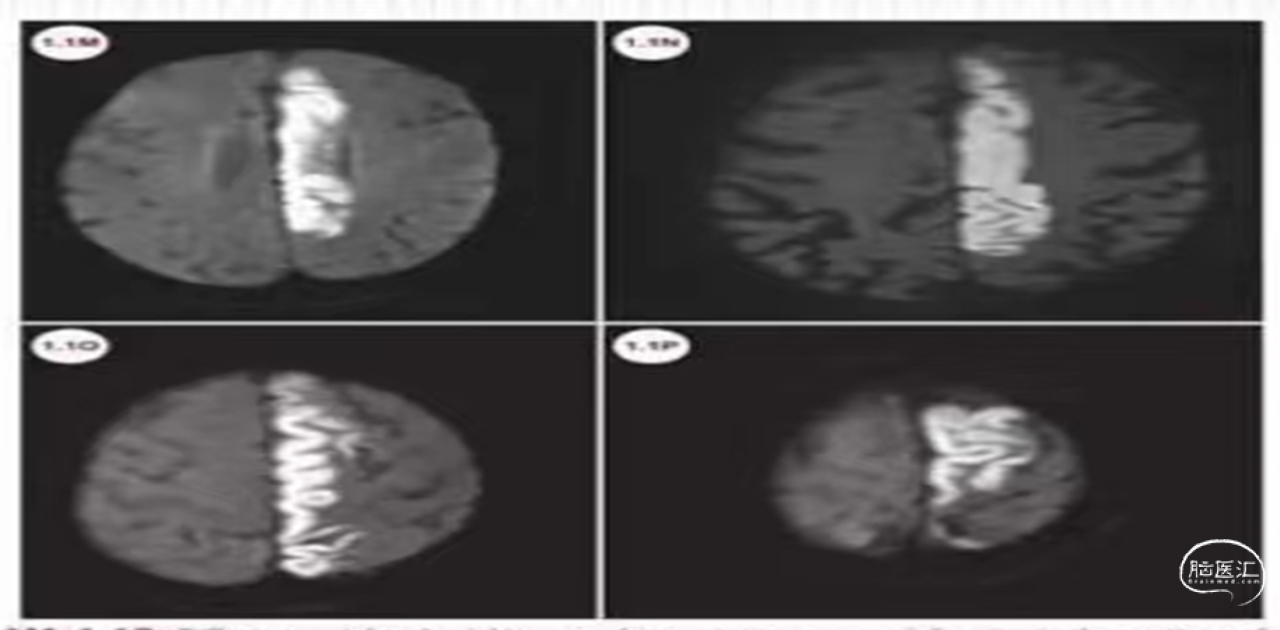

病例简介:患者老年女性,76岁,“突发意识模糊,右侧肢体无力2小时”入院。查体左侧肢体肌力2级,心房颤动,NIHSS评分9分。CT无出血征象。急诊核磁DWI:左侧大脑半球高密度。

诊断:1.心源性栓塞可能;2.左侧大脑中动脉下干急性闭塞。

发病4.5小时内,NiHss评分9分,符合静脉溶栓,体重45kg。

静脉溶栓:给予阿替普酶37.8mg,首剂3.8mg团注,溶栓40分钟能言语,意识明显好转。肌力恢复不明显,牙龈少量出血。

机械碎栓+替罗非班:6Fguiging导引导管置于颈内动脉C1段起到支撑作用,微导丝到达M2段,微导管通过狭窄再回撤。撤出微导丝,微导管内推注替罗非班8ml (1ml/min),再次造影,血流明显改善。术后双联抗血小板聚集+阿托伐他汀、人尿激肽原酶--尤瑞克林治疗10天患者恢复良好,无明显后遗症。

核磁DWI示:左侧大脑中动脉区域大面积梗塞(发白的区域)。

病因:血管狭窄并梗塞可能(左侧大脑中区域较右侧萎缩)。似乎低灌注表现(DWI密度不均,大部分密度不太高)。

评估:发病后2.5小时,CT无出血,NiHss评分19分,为大血管闭塞.符合静脉溶栓+桥接治疗。

静脉溶栓:体重70Kg,给予阿替普酶63mg溶栓(0.9mg/Kg),溶栓30分钟,右侧上下肢肌力恢复为4级,40分钟言语可,略含糊,溶栓有效。

血管内桥接捣栓、碎栓治疗:行脑血管造影,左侧大脑中动脉M1分叉部重度狭窄,但血流通畅。微导丝携带微导管通过狭窄部位,微导管反复回拉。再次造影狭窄明显改善。术后言语略含糊,右侧肢体肌力5-级,经动-静脉桥接治疗病情明显逆转。